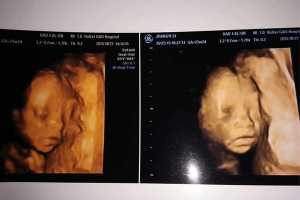

三维彩超

什么是三维彩超 三维彩超,即彩色多普勒超声检查的一种,检查图像呈土黄色,通过多普勒超声仪器发出超声波,对体内各项器官进行成像。三维即其图像是立体的,可以更直观的看到器官的形态,及时发现病变并进行治疗。三维彩超常用于产检,用来判断胎儿的生长发育的情况或是否出现畸形等。 三维彩超检查项目 三维彩超在日常…